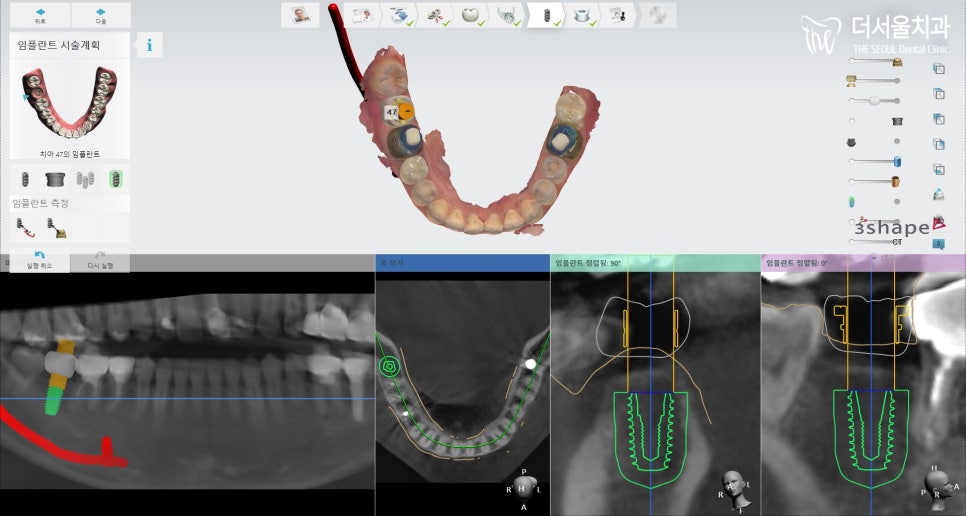

이제는 성남 치과 에서

컴퓨터 분석 프로그램을 이용하여

정확한 위치에 올바른 각으로

심어드리는 게 중요합니다.

이렇게 분석해서 살펴본 결과

신경관과 거리는 괜찮았으며,

46번 치근과 긴밀한 점을 고려하여

더욱 조심스럽게 접근을 해서

식립해드려야 되었습니다.

그외에는 크게 문제될 사항이 없어서

수월히 식립 과정이 이뤄졌습니다.